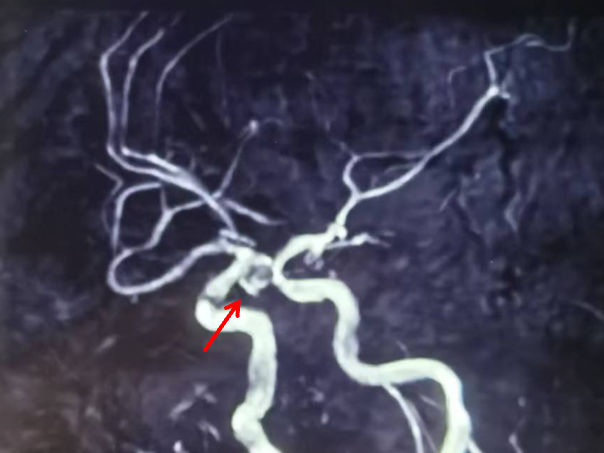

左侧颈动脉正侧位造影:左侧颈内动脉后交通段动脉瘤(箭头所示)。

左侧颈内动脉3D造影可见动脉瘤位于后交通动脉起始处。

3D血管造影可见左侧后交通动脉瘤,大小约7.05×7.47mm,瘤颈3.68mm,考虑胚胎型大脑后动脉。